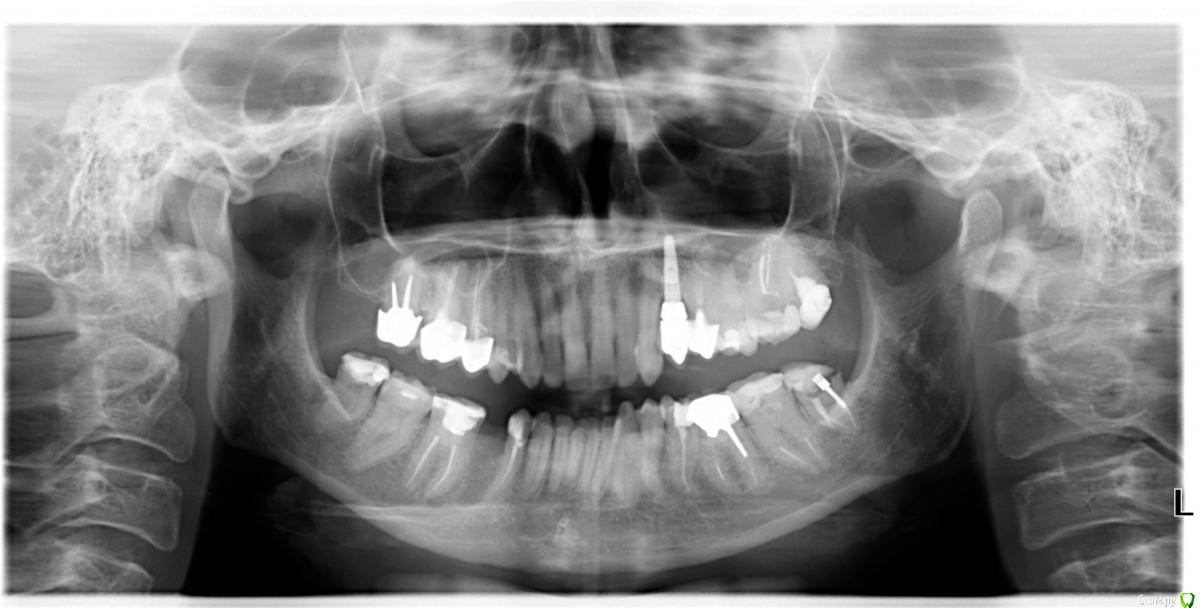

Cleo15 Опубликовано 26 мая, 2020 Поделиться Опубликовано 26 мая, 2020 Добрый день!После удаления нижней пятерки имплантолог на консультации сказал, что корень соседней четверки растет так, что у нас 2 варианта имплантации: либо ставить длинный под наклоном, либо рискнуть установить короткий (10 мм.) вертикально.При этом конструкция под наклоном не столь надежна, как вертикальная вследствие предстоящих проблем с абатментом, а при вертикальной установке существует риск повреждения корня четверки (который я должна взять на себя, следует заметить) плюс долговечность имплантата вследствие его малости также под вопросом.Подскажите, пожалуйста, какой метод предпочтительнее выбрать в такой ситуации? Ссылка на комментарий

Irouil Опубликовано 26 мая, 2020 Поделиться Опубликовано 26 мая, 2020 (изменено) 10 мм - это не короткий имплантат, нужно смотреть КТ, но по этому снимку никаких явных проблем с установкой имплантата я не вижу Зуб давно удалён? Изменено 26 мая, 2020 пользователем Irouil 1 Ссылка на комментарий

Cleo15 Опубликовано 26 мая, 2020 Автор Поделиться Опубликовано 26 мая, 2020 Удален 5 месяцев назад.КТ https://my-files.su/2kio3d Ссылка на комментарий

stommm Опубликовано 27 мая, 2020 Поделиться Опубликовано 27 мая, 2020 10мм имплант в правильной ортопедической позиции предпочтительнее 14 мм импланта в неправильной. И 10 это не короткий. И 8 мм нормальный размер. Короткий это 4 мм длина. Ссылка на комментарий

Bier Опубликовано 28 мая, 2020 Поделиться Опубликовано 28 мая, 2020 таки правильно тут ставить с небольшим наклоном. Длина не имеет значения. Ссылка на комментарий